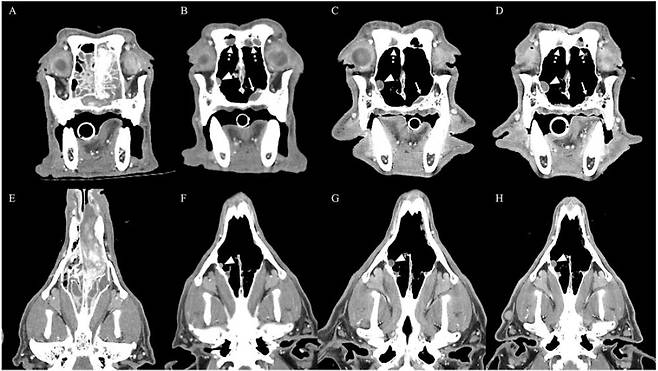

이번 사례의 환자(환견)는 비강(코 안)에서 발생한 육종이 약 2년간 수술과 항암치료 등을 받았음에도 종양이 다시 진행된 상태였다. 추가 치료가 필요한 상황에서 의료진은 보다 효과적인 치료 방법을 찾기 위해 종양 조직을 정밀 분석했다.

검사 결과 종양세포에서 'PDGFR'이라는 특정 수용체가 과도하게 발현된 것이 확인됐다. 의료진은 이를 근거로 해당 수용체를 표적으로 하는 항암제 '소라페닙'을 선택해 치료를 시작했다.

그 결과 환자는 약 4개월 이상 종양이 더 커지지 않는 안정적인 상태를 유지했다.

그러나 치료 약 4개월 후 환자에게 갑작스러운 코피와 호흡 불편 증상이 나타났다. 일반적인 혈액검사와 응고 검사에서는 특별한 이상이 발견되지 않았다. CT(컴퓨터 단층촬영)에서도 종양 악화는 확인되지 않았다.